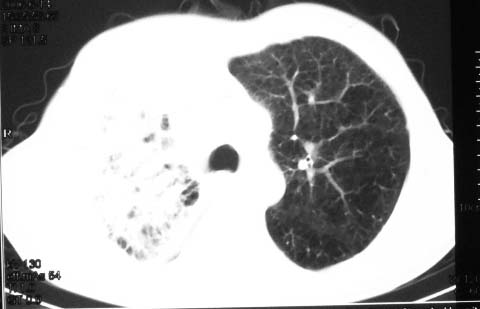

影象表现:右肺上叶大片状、网格状及索条致密影,蜂窝影,其内参杂斑点状小结节,密度不均匀,内见含气支气管像,纵隔内见肿大淋巴结.

抗炎10天后无好转出现胸水,考虑:肺结核合并间质纤维化

抗感染病变无明显改善,右上叶大片状增弥不均匀病灶,夹杂网状及支气管充气像,肺门纵隔淋巴结肿大,右侧胸腔积液。考虑1混合感染伴肺间质改变[警惕特殊感染,如真菌]。2细支气管肺泡癌。建议结合临床及进一步检查[如痰,胸水脱落细胞检查及支气管镜检灌洗或穿刺活检

影象表现:右肺上叶大片状、网格状及索条致密影,蜂窝影,其内参杂斑点状小结节,密度不均匀,内见枯枝样含气支气管像,纵隔内见肿大淋巴结.胸膜广泛增厚,前胸壁似受累.少量胸腔积液.纵隔内淋巴结的直径>1.5cm.右侧胸廓体积缩小.考虑:1 肺结核合并间质纤维化 2 细支气管肺泡癌

右肺上叶大片状、网格状及索条致密影,蜂窝影,其内参杂斑点状小结节,密度不均匀,内见枯枝样含气支气管像,纵隔内见肿大淋巴结.胸膜广泛增厚,前胸壁受累增厚.少量胸腔积液.纵隔内淋巴结的直径>1.5cm.右侧胸廓体积缩小.考虑: 细支气管肺泡癌并肺内癌性淋巴管炎。